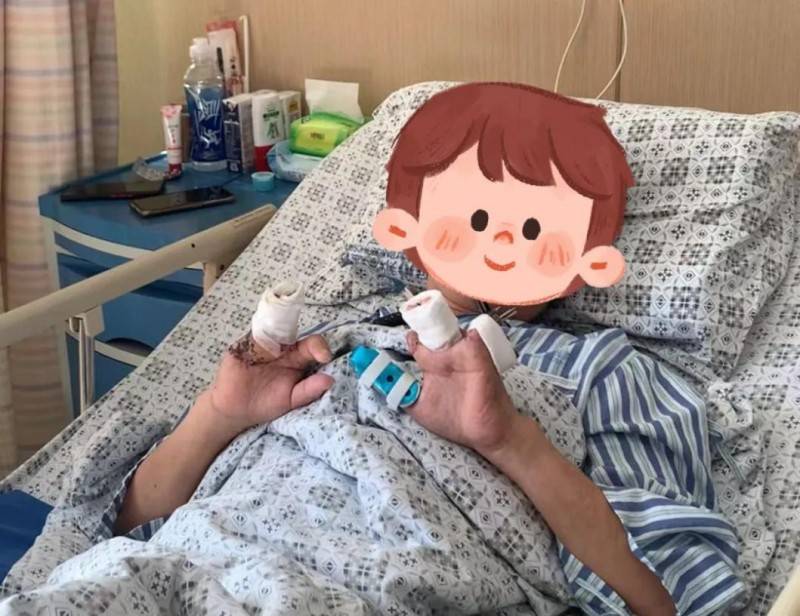

“接上的4根手指,现在吃饭、发信息都是没有啥问题,以后日常生活不成问题!我很满足了。”李先生一边笑着说,一边“展示”可活动的几根手指。李先生的左、右手的中指和无名指(一共4根手指)曾是脚趾,都是从他的脚上取下,移植到左、右手上的。

李先生今年49岁,一直在黄山的一家工厂里当操作工。2024年9月上午,机器皮带突然不转了,李先生用手扒了一下,机器又突然转动了起来,没想到,近4吨重冲床,重重的压了下来,他的左2-5指及右3-5指当时就被击掉了。

李先生在本地医院进行了前期的治疗后,即刻被家人送到了杭州邦尔骨科医院。“当时患者的左手的2-5指和右手3-5指离断,缺损非常严重。”杭州邦尔骨科医院手外科宋杰主任介绍。当时宋杰主任一边处理李先生的残端伤口,一边考虑为李先生将断指重新接上,可一问才得知,断指没了!

原来,李先生受伤后,疼痛难忍、血流不止,几个工友只忙着照顾他,没想着要找到、保存断指。考虑到缺的手指较多,以及功能的重要性,宋杰主任建议李先生将每个脚取2个脚趾进行再造,后期行左手第2指第5指延长术,通过这些方案来恢复他的手的完整性和功能。

“把我的脚趾变成手指头?”李先生头一次听到有这样的手术,虽然心里觉得有点别扭,但他最后还是听从了宋杰主任的建议。手术最难的其实就是血管吻合部分,每根血管的外径只有0.4毫米—0.5毫米,借助显微镜每根血管上要缝4针—6针。